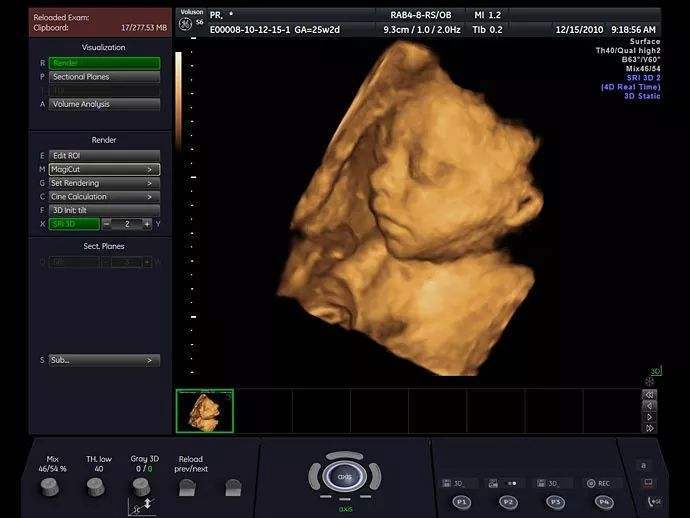

令人惊叹的未出生胎儿照片